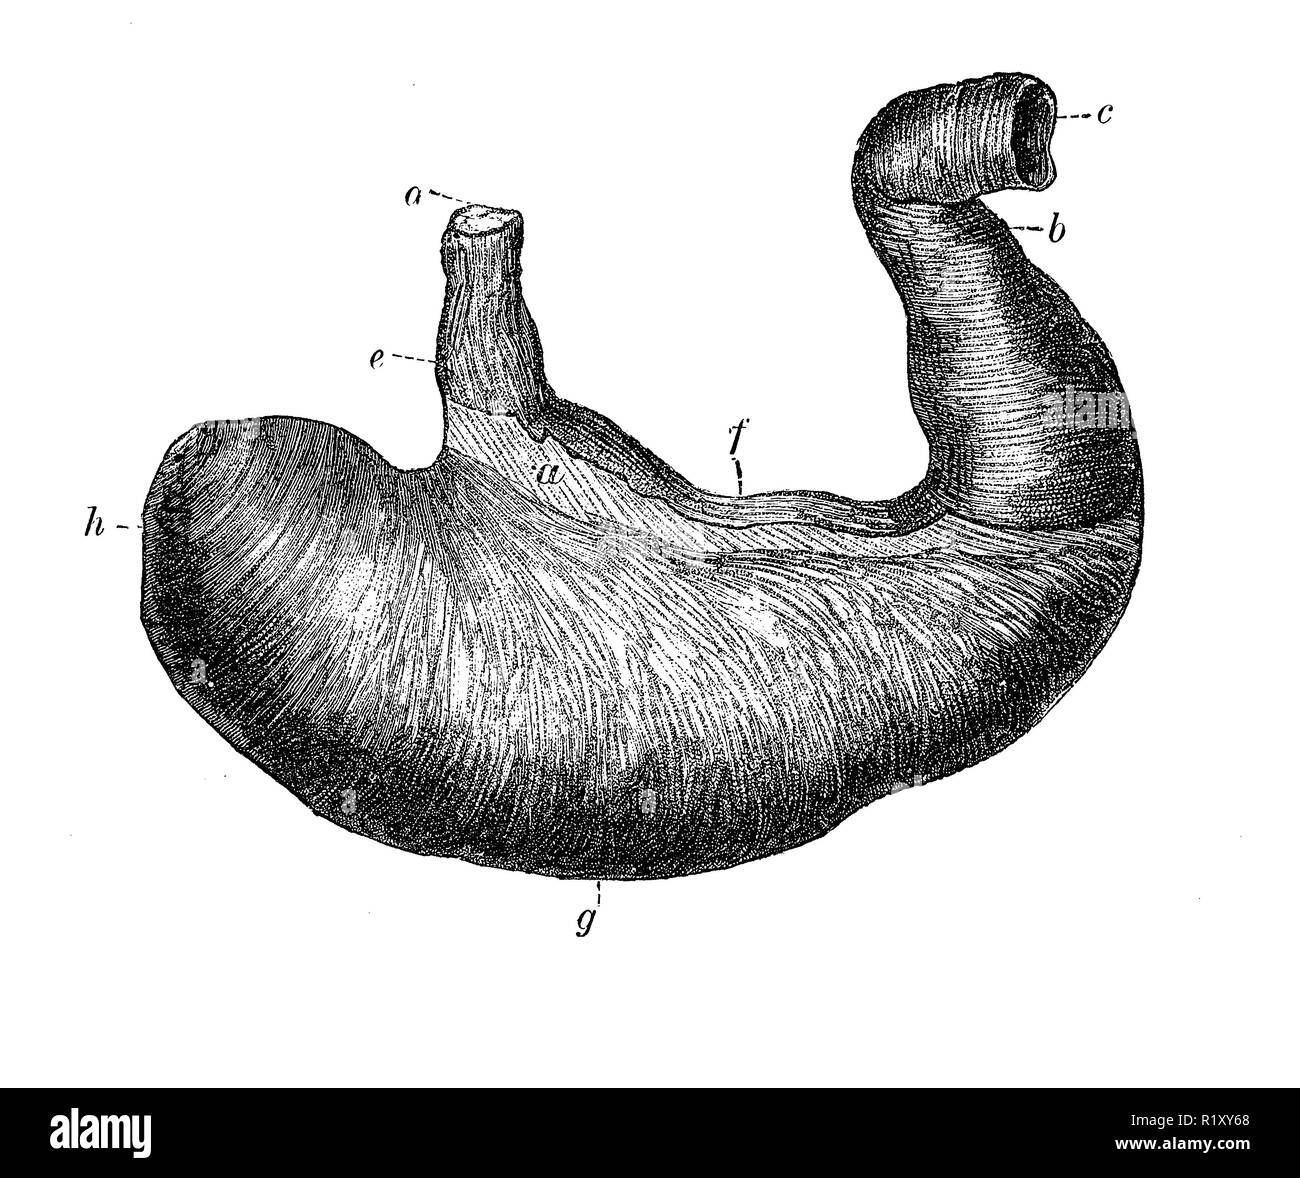

Vintage illustration of anatomy, human stomach Stock Photohttps://www.alamy.com/image-license-details/?v=1https://www.alamy.com/vintage-illustration-of-anatomy-human-stomach-image224941536.html

Vintage illustration of anatomy, human stomach Stock Photohttps://www.alamy.com/image-license-details/?v=1https://www.alamy.com/vintage-illustration-of-anatomy-human-stomach-image224941536.htmlRFR1XY68–Vintage illustration of anatomy, human stomach